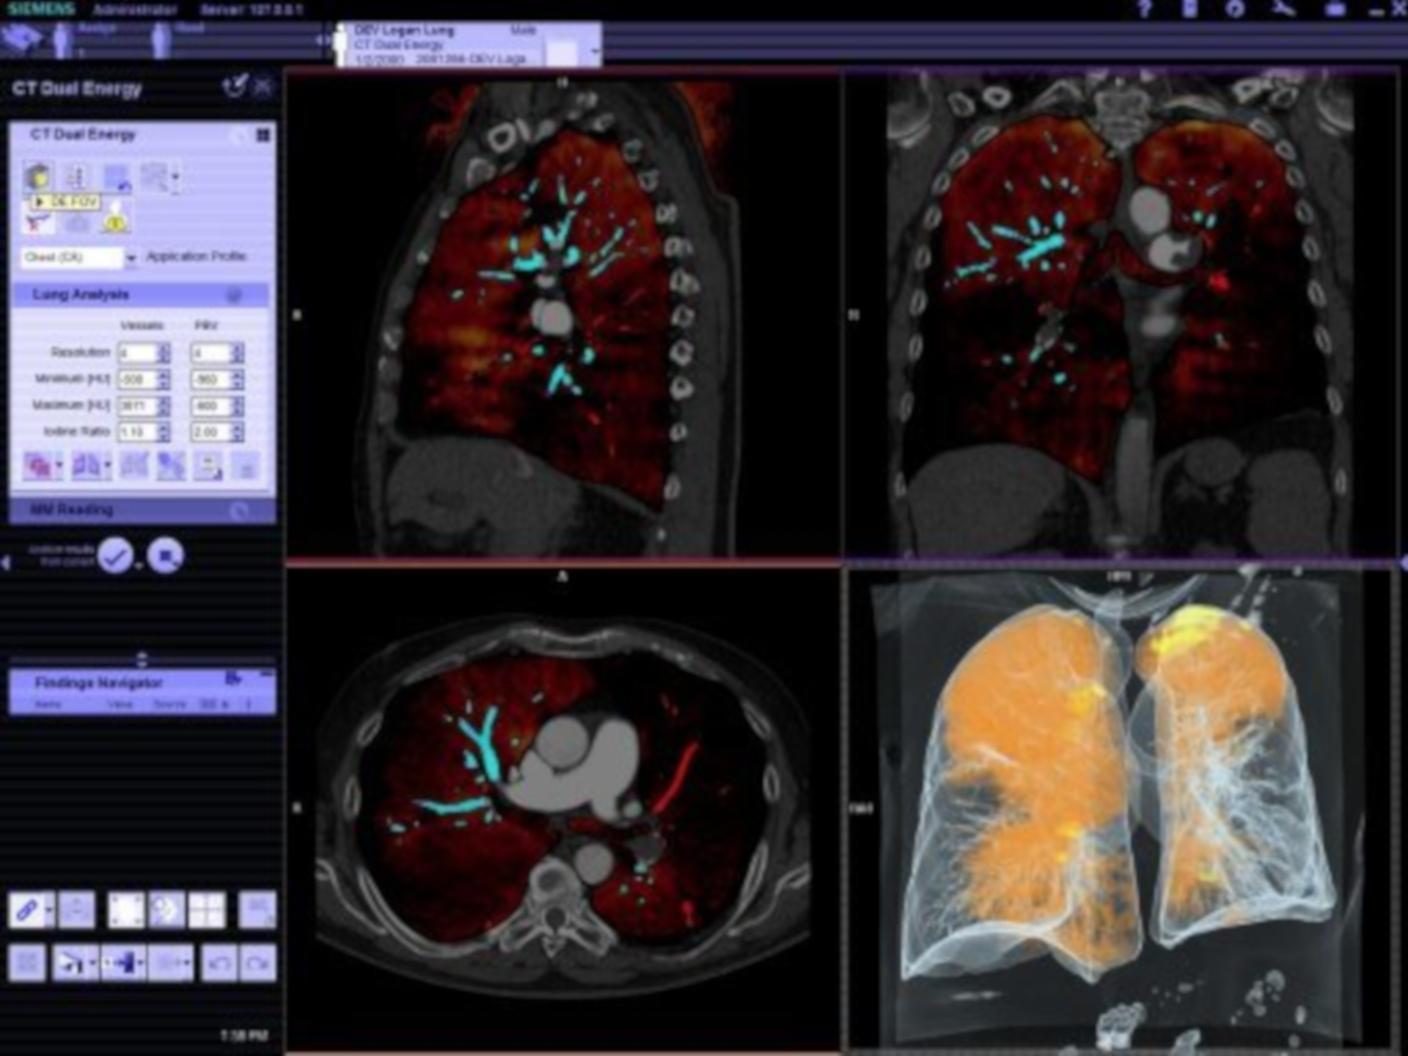

Options & Upgrades for your Computed Tomography system

Browse our clinical software applications for Computed Tomography or request a trial license.